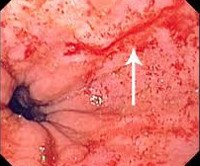

• Эзофагогастроскопия. Введение гибкого эндоскопа через полость рта позволяет оценить состояние эпителиальной мембраны верхних отделов желудочно-кишечного тракта и выявить линейные разрывы, которые обычно расположены в зоне перехода пищевода в желудок. При визуальном осмотре можно определить глубину поражения стенки пищевода или желудка.